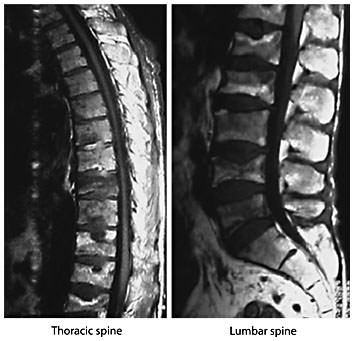

Osteoporosis: Immunologic Aspects

Osteoporosis is defined as a skeletal disorder characterized by compromised bone strength predisposing a person to an increased risk of fracture. Bone strength primarily reflects the integration of bone density and bone quality [197]. Osteoporosis is among the most important conditions associated with aging; the lifetime risk for a fragility fracture (vertebral fracture (fig. 3), distal forearm fracture, hip fracture) in a 50-year-old white US woman is approximately 40%, whereas that in a white US man is 13% [198].

Magnetic resonance images of the thoracic and lumbar spine. Magnetic resonance study of the thoracic and lumbar spine of a man with multiple vertebral fractures due to osteoporosis. Courtesy of Prof. Dr. H. Resch, Department of Medicine 2, St. Vincent Hospital, Vienna.

Magnetic resonance images of the thoracic and lumbar spine. Magnetic resonance study of the thoracic and lumbar spine of a man with multiple vertebral fractures due to osteoporosis. Courtesy of Prof. Dr. H. Resch, Department of Medicine 2, St. Vincent Hospital, Vienna.